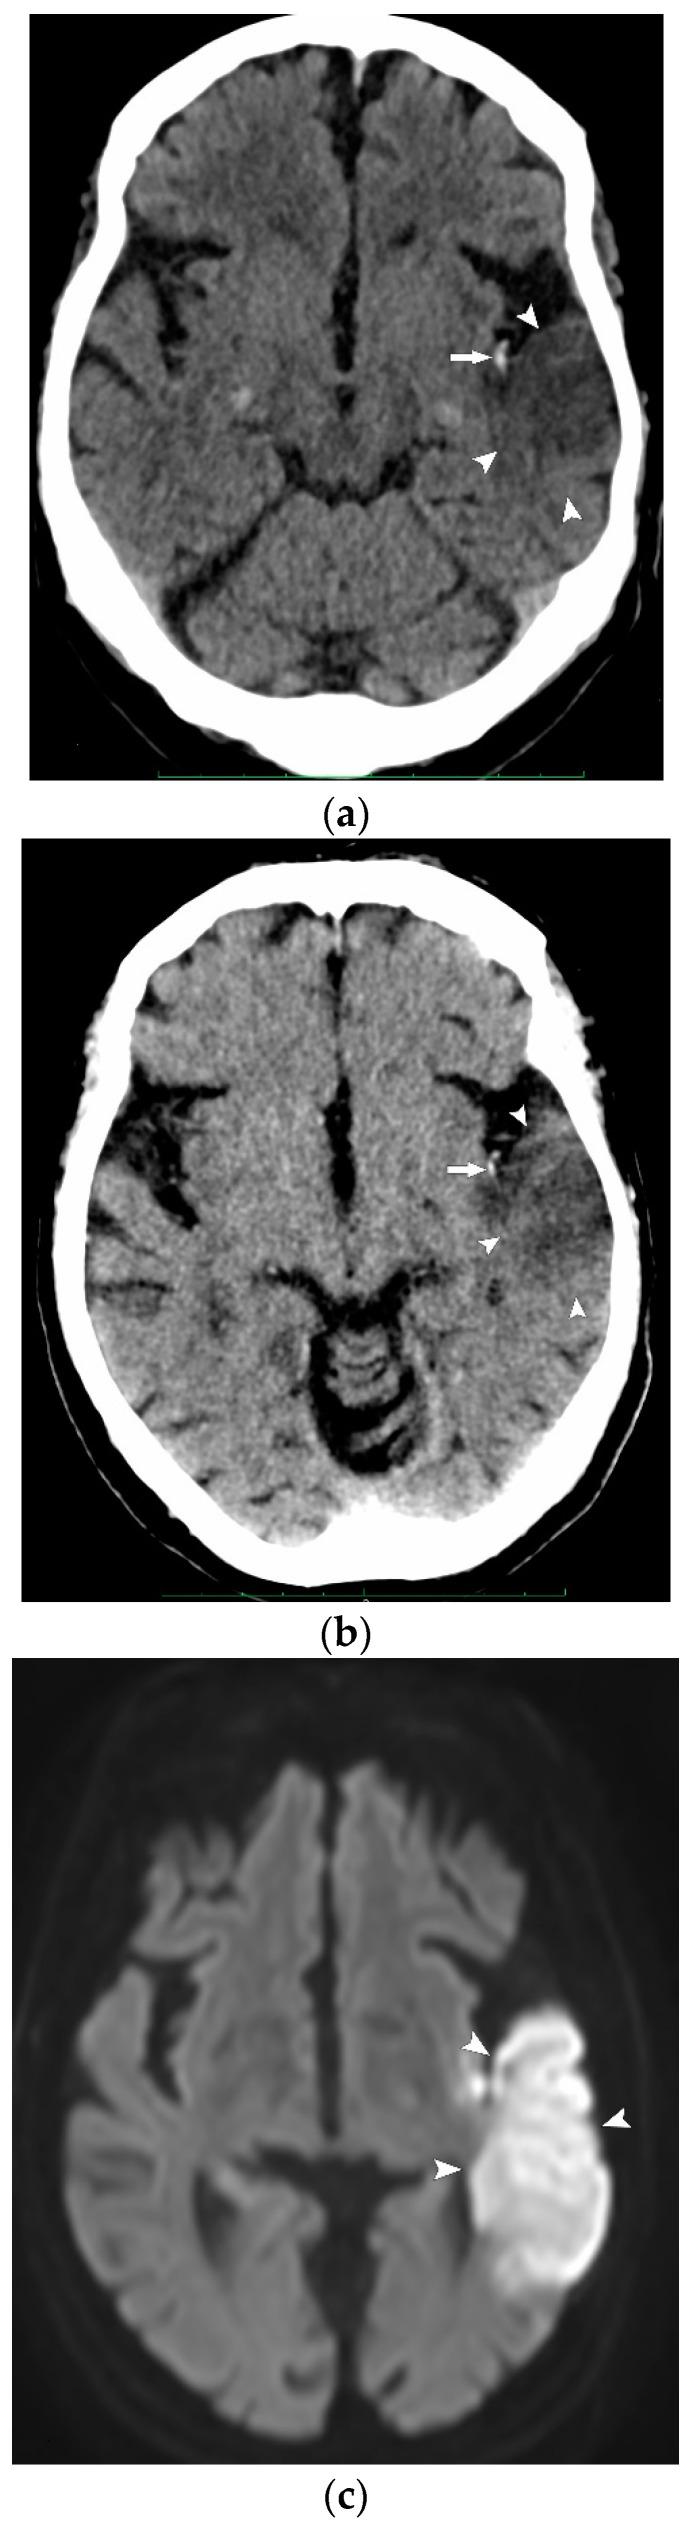

We aimed to evaluate whether virtual non-contrast cerebral computed tomography (VNCCT) reconstructed from intravenous contrast-enhanced dual-energy CT (iv-DECT) could replace non-contrast CT (NCCT) in patients with suspected acute cerebral ischemia. This retrospective study included all consecutive patients in whom NCCT followed by iv-DECT were performed for suspected acute ischemia in our emergency department over a 1-month period. The Alberta Stroke Program Early CT Score (ASPECTS) was used to determine signs of acute ischemia in the anterior and posterior circulation, the presence of hemorrhage, and alternative findings, which were randomly evaluated via the consensus reading of NCCT and VNCCT by two readers blinded to the final diagnosis. An intraclass correlation between VNCCT and NCCT was calculated for the ASPECTS values. Both techniques were evaluated for their ability to detect ischemic lesions (ASPECTS <10) when compared with the final discharge diagnosis (reference standard). Overall, 148 patients (80 men, mean age 64 years) were included, of whom 46 (30%) presented with acute ischemia, 6 (4%) presented with intracerebral hemorrhage, 11 (7%) had an alternative diagnosis, and 85 (59%) had no pathological findings. The intraclass correlation coefficients of the two modalities were 0.97 (0.96-0.98) for the anterior circulation and 0.77 (0.69-0.83) for the posterior circulation. The VNCCT's sensitivity for detecting acute ischemia was higher (41%, 19/46) than that of NCCT (33%, 15/46). Specificity was similar between the two techniques, at 94% (97/103) and 98% (101/103), respectively. Our results show that VNCCT achieved a similar diagnostic performance as NCCT and could, thus, replace NCCT in assessing patients with suspected acute cerebral ischemia.

我们旨在评估从静脉注射对比剂的双能量CT(iv-DECT)重建的虚拟非增强脑计算机断层扫描(VNCCT)能否替代疑似急性脑缺血患者的非增强CT(NCCT)。这项回顾性研究纳入了在1个月内于我们急诊科因疑似急性缺血而先后进行NCCT和iv-DECT检查的所有连续患者。使用阿尔伯塔卒中项目早期CT评分(ASPECTS)来确定前循环和后循环中急性缺血的征象、出血情况以及其他发现,由两名对最终诊断不知情的读者通过对NCCT和VNCCT的一致性解读进行随机评估。计算VNCCT和NCCT的ASPECTS值之间的组内相关性。将两种技术与最终出院诊断(参考标准)进行比较,评估它们检测缺血性病变(ASPECTS<10)的能力。总体而言,共纳入148例患者(80例男性,平均年龄64岁),其中46例(30%)出现急性缺血,6例(4%)出现脑出血,11例(7%)有其他诊断,85例(59%)无病理发现。两种模式在前循环的组内相关系数为0.97(0.96 - 0.98),后循环为0.77(0.69 - 0.83)。VNCCT检测急性缺血的敏感性高于NCCT,分别为41%(19/46)和33%(15/46)。两种技术的特异性相似,分别为94%(97/103)和98%(101/103)。我们的结果表明,VNCCT在诊断性能上与NCCT相似,因此在评估疑似急性脑缺血患者时可以替代NCCT。